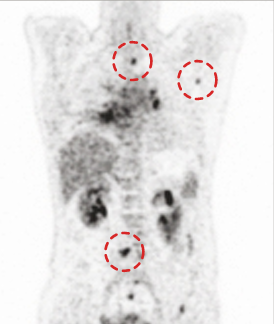

CASE #3

15 min (50%) Scan Without Denoising

15 min (50%) Scan With Denoising

30 min (100%) Scan Standard